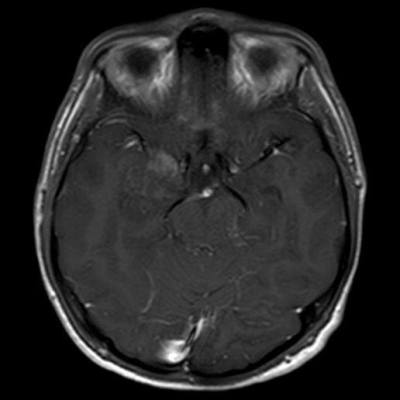

- A) Sağ temporal lob anteromedialinde silik sınırlı BT’de hipodens (ok), MRG’de T2AG ve FLAIR hiperintens (oklar), T1AG izo-hipointens (ok) sinyal özelliğinde ekspansil kitlesel lezyon izlenmektedir.

- MRG: T1A serilerde solid komponent izo-hipointens, T2A serilerde genellikle hiperintens sinyalde görülür. Peritümöral T2/FLAIR hiperintens kitle ödemi oldukça nadirdir. T1 C+ görüntülerde solid komponentte değişken oranda kontrastlanma ,T2*(SWI) serilerde eğer kalsifikasyon eşlik etmekteyse buna bağlı blooming artefaktları görülebilir.